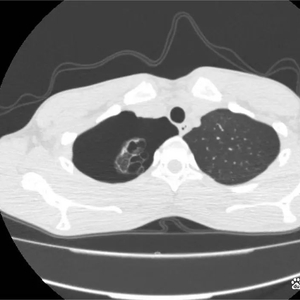

胸膜腔内积气称为气胸,多是由于肺组织、气管、支气管、食管破裂,空气逸入胸膜腔,或因胸壁伤口穿破胸膜,外界空气进入胸膜腔所致。根据胸膜腔损伤及压力情况,气胸可分为闭合性气胸、开放性气胸和张力性气胸三类。

青少年自发性气胸多为闭合性气胸,胸腔内积气量直接决定肺压缩程度,当气胸出现时,被气体挤压收缩的肺无法进行正常的通气换气,轻者无明显症状,重者可能出现呼吸困难。体格检查时可发现伤侧胸廓饱满,呼吸活动度下降,胸部叩诊呈鼓音,听诊呼吸音明显减弱。

自发性气胸通常是由肺表面大疱破裂致使正常呼吸时入肺的气体通过破损处进入胸腔导致, 普遍好发于瘦高体型的人群,在青少年或青壮年等经常运动的群体中多见。肺大疱常见于双肺肺尖表面,因青春期胸廓和肺的生长发育速度差距过大,导致肺尖等张力过大处的表面肺组织发育畸变,进而形成肺大疱。 若在剧烈运动后出现胸腔内刺痛、胸闷、咳嗽等症状,应高度警惕肺大疱破裂导致的自发性气胸的可能性。

●若经影像学检查积气量不多(肺压缩不超过30%),可考虑暂保守观察。

●若积累气体过多,严重压迫肺组织,则需要胸腔穿刺等引流治疗。